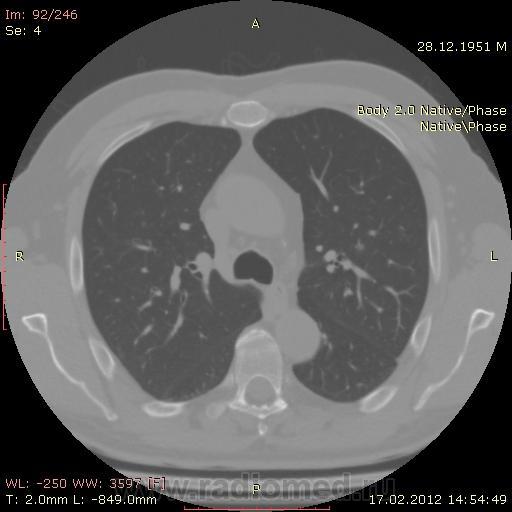

КТ.

В феврале 2012 года при очередном флюрографическом обследовании были обнаружены изменения в лёгких. По собственной инициативе было сделано КТ лёгких.

На первый взгляд - метастазы. А так, если родственник, искать выходы на МСКТ.

Согласен с Андреем Юрьевичем - наиболее вероятно - это метастазы...исключите первичное новообразование почки.

Согласен с коллегами, внешне вылитые метастазы. Но почему нет контраста? Не соли мочевой кислоты точно. Учитывая анамнез можно думать о неопроцессе почек.

Одну почку (левую) удалили по причине светло-клеточного рака.

Повторяюсь (мнение озвучил еще до КТ и до Ваших коментов) но это отдаленные по времени метастазы рака почки....увы....и даже если будет найден еще один первичный очаг, то все равно это - метастазы...опять - увы....